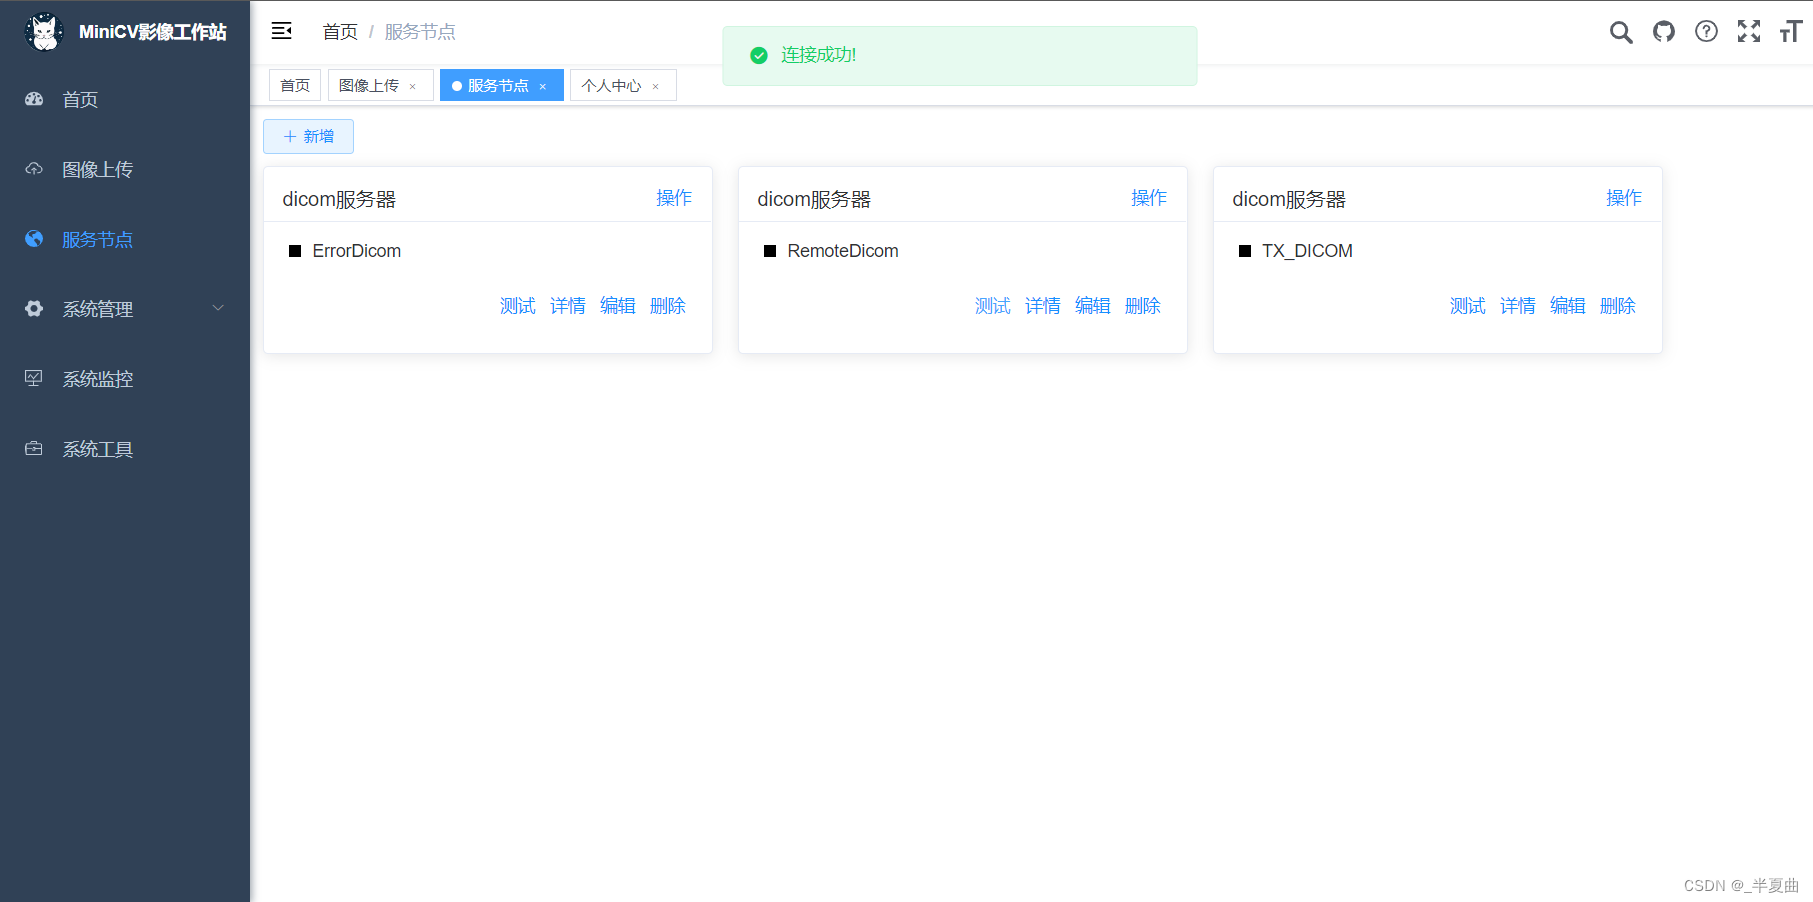

Dicom服务器动态配置功能;

DICOM服务节点维护: